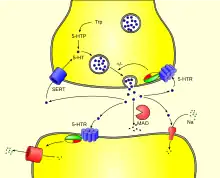

La biosynthèse de la sérotonine est réalisée dans les neurones ou les cellules entérochromaffines. Elle est fabriquée à partir du tryptophane (Trp), un acide aminé qui est apporté au cerveau par la circulation sanguine entre autres. Le tryptophane est absorbé par les neurones grâce à un transporteur membranaire non sélectif. Certains neurones du noyau du raphé, situé au sein du tronc cérébral, transforment le tryptophane en 5-hydroxytryptophane (5-HTP) grâce à une enzyme, la tryptophane hydroxylase. L'activité du tryptophane hydroxylase dépend essentiellement de la disponibilité en substrat. Le 5-hydroxytryptophane est ensuite converti en sérotonine (5-HT) par une autre enzyme, une décarboxylase, la 5-hydroxytryptophane décarboxylase (L-amino acide décarboxylase, AADC). Cette enzyme n'est pas sélective car elle assure aussi la décarboxylation de la L-dopa. La sérotonine synthétisée dans le cytoplasme est ensuite stockée dans les granules par l'intermédiaire de transporteurs vésiculaires, nommés VMAT-1 et -2, communs aux diverses monoamines.

L'arrivée d'un potentiel d'action à la terminaison synaptique provoque la libération de la sérotonine par exocytose, dans la fente synaptique. Elle peut alors suivre quatre voies :

- être captée par des récepteurs sérotoninergiques postsynaptiques et assurer la transduction du signal neuronal ;

- être recaptée par des récepteurs sérotoninergiques présynaptiques ;

- être recaptée par des neurones (ou des plaquettes) par l'intermédiaire d'un transporteur membranaire sélectif SERT ;

- être dégradée par la monoamine oxydase MAO.

La MAO dégrade aussi les catécholamines. L'aldéhyde formé est ensuite oxydé en acide 5-hydroxy-indol-acétique (5-HIAA), éliminé par voie urinaire, grâce à l'aldéhyde déshydrogénase.

Recapture

La sérotonine déversée dans la fente synaptique peut être recapturée par le neurone présynaptique grâce à un transporteur (SERT) qui diminue ainsi la concentration de sérotonine synaptique. Cette recapture est inhibée par plusieurs antidépresseurs, notamment les ISRS (inhibiteurs sélectifs de la recapture de la sérotonine) qui sont : la fluoxétine, le citalopram et son énantiomère l'escitalopram, la fluvoxamine, la paroxétine et la sertraline.